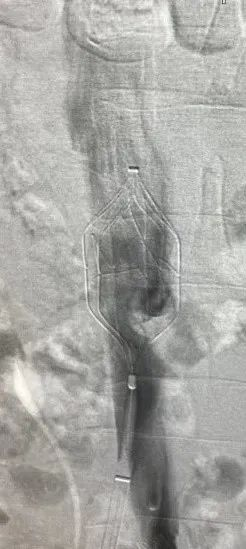

手术过程:

患者取仰卧位,在局部麻醉下经左侧股静脉穿刺完成术前造影,结果显示滤器内血栓负荷较重。随后,经右侧颈静脉入路成功置入血栓保护装置,血栓保护装置距离滤器约3cm,确保术中脱落的血栓能够被有效拦截。使用导管对滤器内血栓抽吸后,通过股静脉路径顺利回收滤器。术后造影检查发现血栓保护装置内成功拦截到血栓,经颈静脉路径负载血栓回收血栓保护装置并将其撤出体外,最终确认下腔静脉通畅无异常。

术前造影

滤器内有血栓